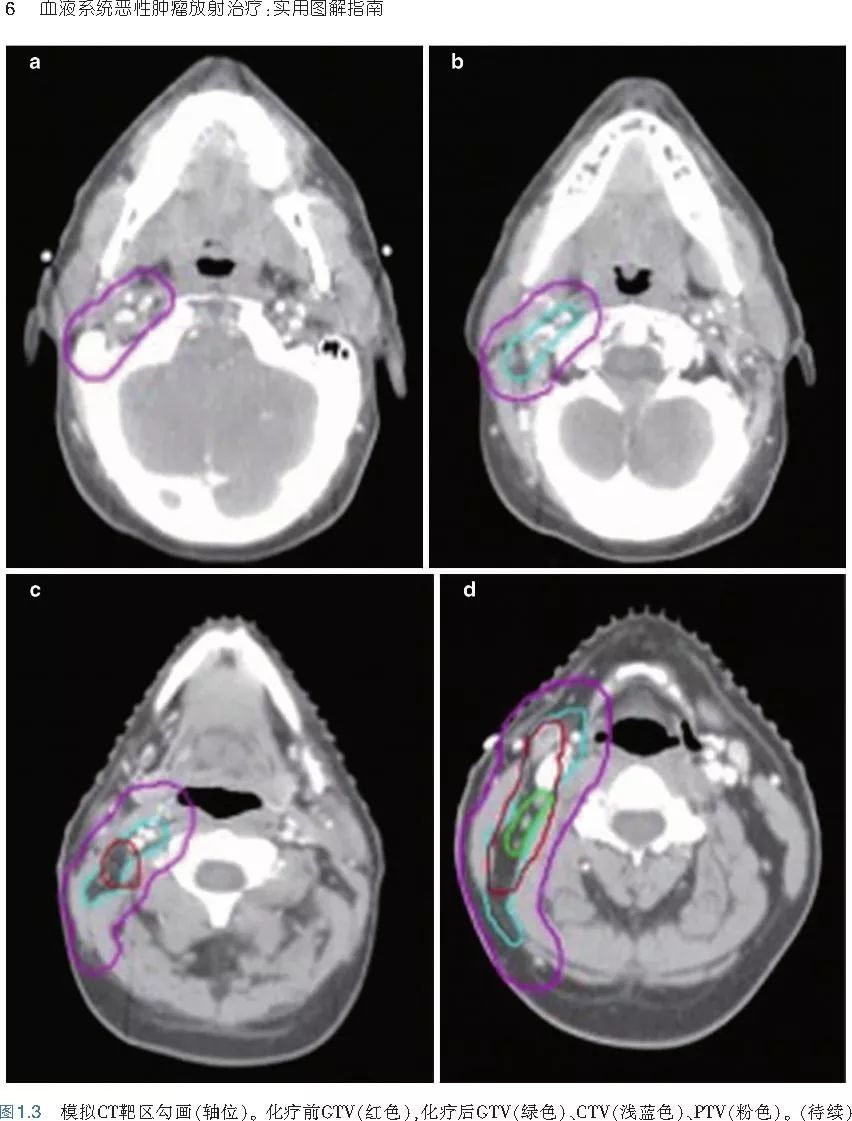

本书旨在帮助临床医生对常见血液系统恶性肿瘤疑难病例进行管理,包括霍奇金淋巴瘤、非霍奇金淋巴瘤和白血病患者,并通过多个病例进行阐述。案例讨论遵循标准格式,包括临床描述,其次是与诊断相关的病理描述和分期,然后详细讨论治疗选择。最后,确定治疗方案,并提供所使用的规划放疗技术/方式的图像。对放射肿瘤医生进行临床决策非常有帮助,对于血液病临床医生也有很好的指导作用。

近年来,放射治疗技术得到了迅速发展,调强放疗、图像引导放疗及其他新技术方法等,对恶性肿瘤治疗产生了巨大影响。现代放疗技术使精确定位、靶区勾画及给量成为可能,实现了肿瘤局控率和生活质量的双赢,对血液系统恶性肿瘤的临床治疗也产生了一定的影响。此书内容上不仅反映了血液系统恶性肿瘤综合治疗的进步,更是对其中放射治疗的新变化进行了系统、详细的阐述,这对当前血液系统恶性肿瘤放射治疗临床实践具有非常好的指导作用和参考价值。